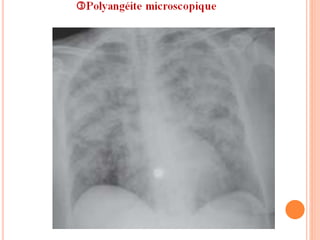

Imagerie thoracique (F+P, TDM):

 Au TLX: opacités bilatérales, généralement symétriques, mais

parfois asymétriques (voire unilatérales). Apex et angles

costodiaphragmatiques relativement épargnés.

 Au TDM:

 Verre dépoli +++ localisation centrale

 Condensations épargnant la périph

 Micronodules centrolobulaires

(au stade plus tardif résorption de l’Hgie

dans l’interstitium).

RP normale

Importance des coupes fines +++